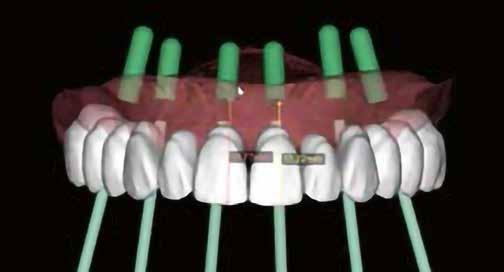

A-PRF membránokkal borítottuk (7. ábra). A mukogingivális lebenyt – annak megnyújtása nélkül – a helyére fektettük és varratokkal rögzítettük, per primam sebzárást nem végeztünk (8., 9. ábra). A varratokat 2 hét után távolítottuk el, a varratszedésig a sebgyógyulás támogatására per os 1000 mg/nap C- és 12 000 NE/nap D-vitamint adtunk (20). A műtéti beavatkozást 24 hét gyógyulási időszak követte, melynek során sem helyi, sem gyógyszeres kezelés nem történt, az esztétikum javítása érdekében a páciens ideiglenes kivehető fogpótlást használt. A csontos gyógyulás ellenőrzése és az implantáció tervezése céljából állcsonti CT felvételt készítettünk, illetve lenyomatvételt végeztünk. A CT felvételen tökéletes csontos gyógyulást észleltünk, az alveolaris csont volumene teljes mértékben megtartott volt (10. ábra), a klinikai kép is ennek megfelelően alakult (11., 12. ábra)

A Trishape Implant Studio™ a korábbi csont augmentáció területén, a felső állcsontnál áltagosnak számító D2-D3 csontminőséget jelzett (13. ábra). A lenyomat alapján készített gipszmodellt szkennelve virtuális mintát nyertünk. A CBCT felvétel és a virtuális modell adatait a Dual Scan protokoll (21) elveinek megfelelően használtuk fel az implantációs sablon (New Age Dental Kft, Nemeskéry Károly) készítéséhez (14., 15., 16. ábra). Az implantátum (Ankylos C/X A11) behelyezése teljesen navigált módon, 35 Ncm primer stabilitással történt (17., 18. ábra). Az implantátumra a fogtechnikus (D1 Dental Kft., Garamvári Csaba) által előzetesen

A navigált implantátumbehelyezés és azonnali ideiglenes korona

A navigált implantátumbehelyezéssel és a protetikai szempontból ideális implantátum-pozíció elérésén túl célunk az

azonnali ideiglenes restaurátum készítése is volt. Az implantátumon rögzített, azonnali ideiglenes korona lehetőséget nyújt a lágyrészek megtámasztására, továbbá a definitív protetikai ellátáshoz szükséges emergencia profil alakítására, emellett egyúttal jelentősen javítja a páciens komfortját. Hangsúlyozni kívánjuk, hogy amennyiben az implantátum behelyezésével egy időben ideiglenes koronát adunk át, a csontminőségtől függetlenül, mindig a következő alapelveket követjük: